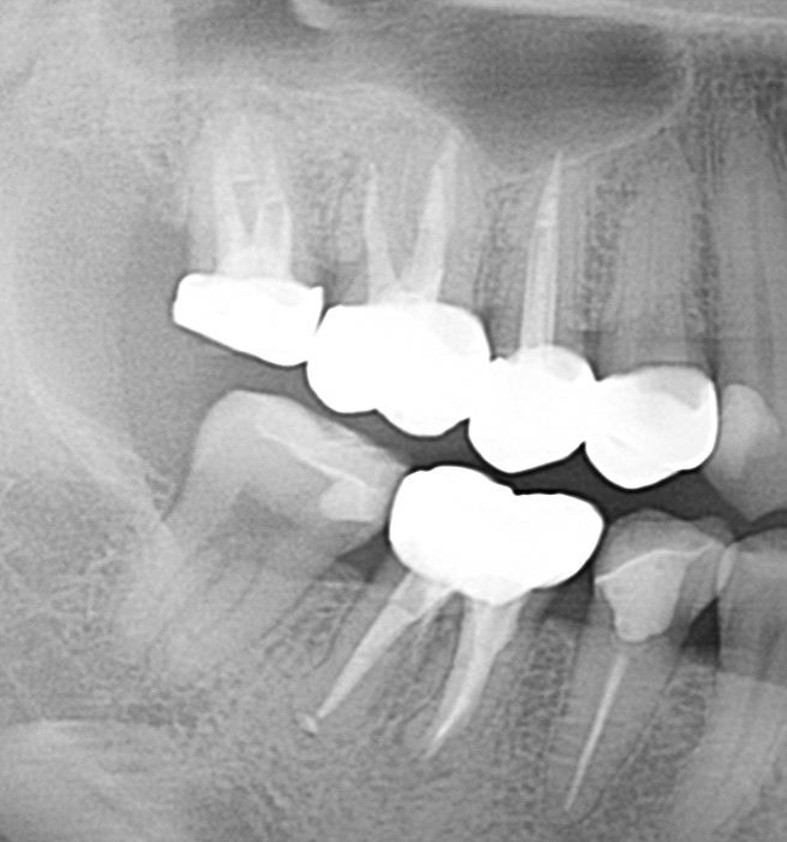

症例7

| 項目 | 詳細 |

|---|---|

| 患者様データ | 50代 男性 |

| 来院時の主訴 | 「右上の歯が噛むと少し痛い。」 |

| 医院の診断 |

虫歯の再発、未処置根管の存在 |

| 通院期間 | 4か月 |

| 来院回数 | 5回 |

| 治療費 | 220,000円(税抜) 《内訳》 精密感染根管治療80,000円、ファイバーポストコア20,000円、セラミック治療120,000円 |

| リスクと副作用 | ①根管治療歯は長期的には破折するリスク ②メインテナンスが必要 |

| ココがこだわりのポイント☝ |

上顎の小臼歯は1根か2根が通常ですが、この歯の場合なんと3根!それも途中で分岐しており4根管ありました。 これはかなりの確率で1%未満と思われます・・・術前のCT検査で発見されました。 そんな歯をラバーダム防湿とマイクロスコープを使用して丁寧に治療を行いました。 再根管治療のため、殺菌性があり歯を補強することのできる根管充填材料を使用しています。 |